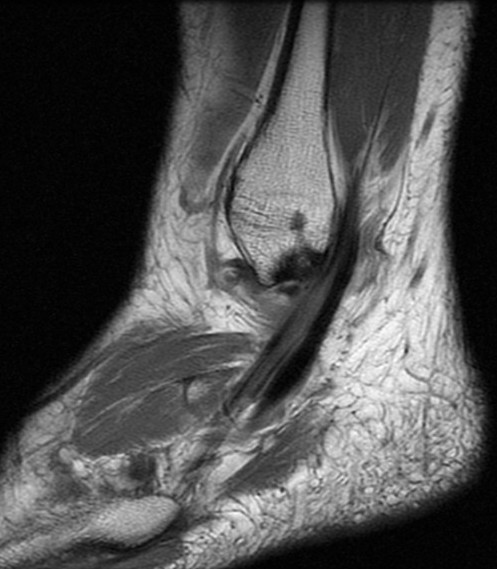

Figure 3 for case Peroneus brevis split tear

Figure 3

41 y/o avid bowler. Nice split tear from the lateral malleoulus tip down past the peroneal tubercle. Reactive tenosynovitis.

Peroneus brevis split tear